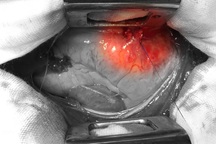

TS.BS Nguyễn Duy Tân, Trưởng khoa Ngoại tim mạch - Lồng ngực cho biết, ekip phẫu thuật đã mổ chẻ xương ức khẩn cấp để khâu lại các vết thủng tim, phổi.

Các bác sĩ phẫu thuật cho bệnh nhân bị đâm thủng tim, phổi (Ảnh: Bệnh viện cung cấp).